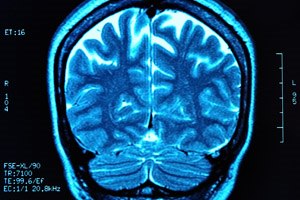

פגיעה מוחית עלולה לגרום לליקוי בזיכרון, גם כשאין לכך ממצאים...

מדריך בדיקות רפואיות: טומוגרפיה ממוחשבת של הראש מסייעת...